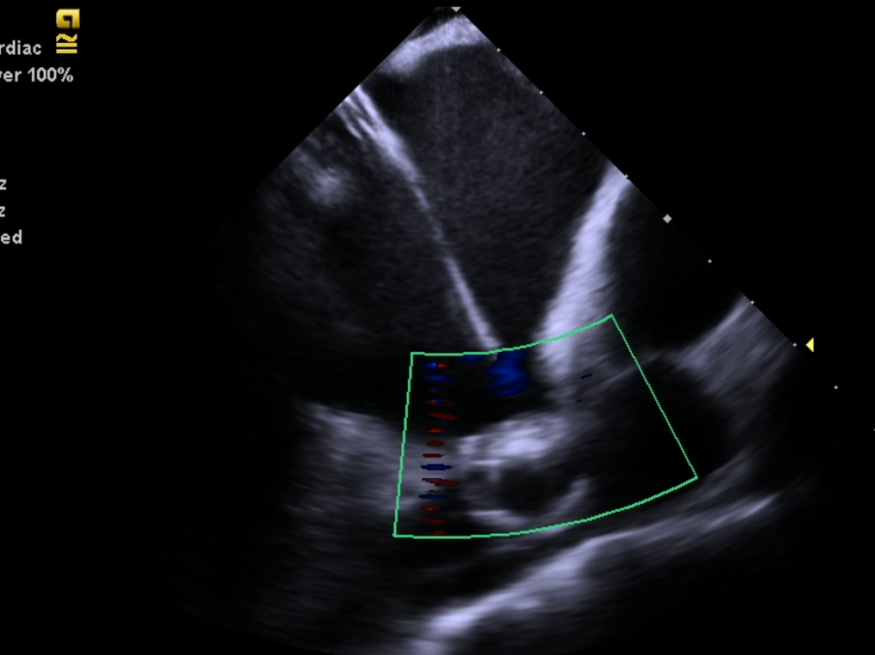

近年来心腔内三维超声技术(ICE)是国际心内介入领域兴起的一项新技术。它在心内导管介入的基础上,把腔内超声探头送到心脏的特定部位,结合心腔内三维标测技术对于用于复杂的心律失常的治疗和房颤治疗。让医生得以在手术中清晰观察心脏内的特殊结构,实时监测心脏情况。被誉为潜入心脏的眼睛,术者可以慧眼识心,患者安全倍增。

2021年6月17日中午12:30,88岁高龄的患者在局麻下,经心腔内超声(ICE)引导行左心耳封堵。术程顺利。当手术结束后,心内科导管室内所有医护人员都不约而同地为彭建军主任精彩而成功的手术鼓起掌来。